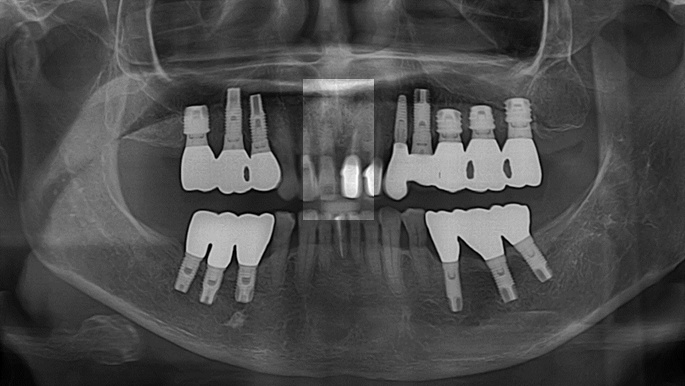

Clinical case: : Immediate loading of lower molars using R2Gate prefabricated 3D-printed provisional restoration

- Courtesy of Dr. Sam Omar, Egypt -

Dr.Sam Omar, immediate loading, digital guided surgery, digital ONE-DAY implant, maxillary anterior, #21, guided surgery, immediate loading, AnyRidge, R2GATE, Mega ISQ, MEG Torq, R2GATE Full Surgical Kit

implant system, R2GATE Guide, R2GATE surgical kit (AnyRidge), Mega ISQ

“ONE-DAY implant, one-day smile